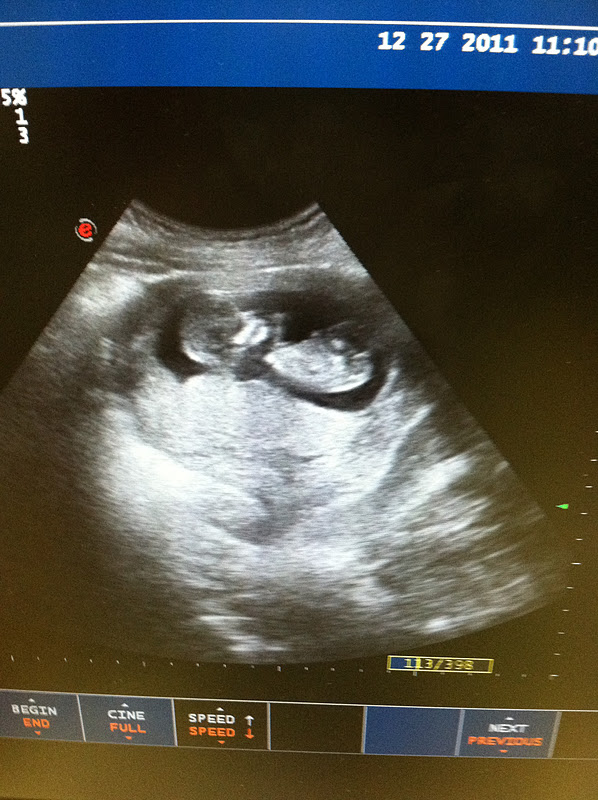

For my twelve week check-up my doctor did an ultrasound and we got to see the baby. Layne and Ethan were there with me. The baby was moving all over the place and actually resembled a little baby. So stinking cute!